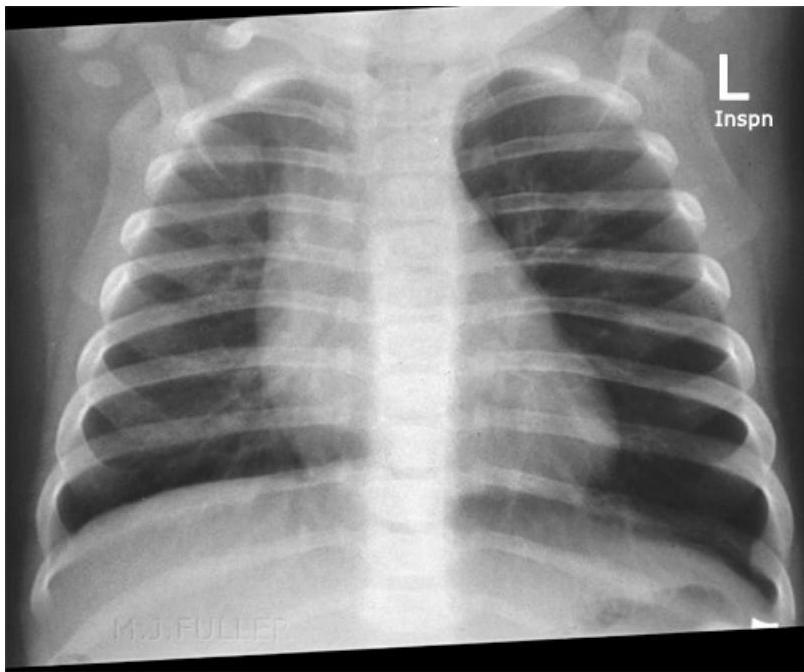

- Expiratory Chest X-ray or Fluoroscopy:

- Indicated for children with a suggestive presentation but normal inspiratory X-ray.

Radiological Findings:

- On Inspiration: Lungs may appear similar as airways widen, allowing air past the FB.

- On Expiration: The FB can obstruct the bronchus as its diameter decreases. The greatest difference in lung aeration is seen here, as air is trapped in the affected lung while exhaled from the normal lung.

- Hyperinflated lung

- Mediastinal shift